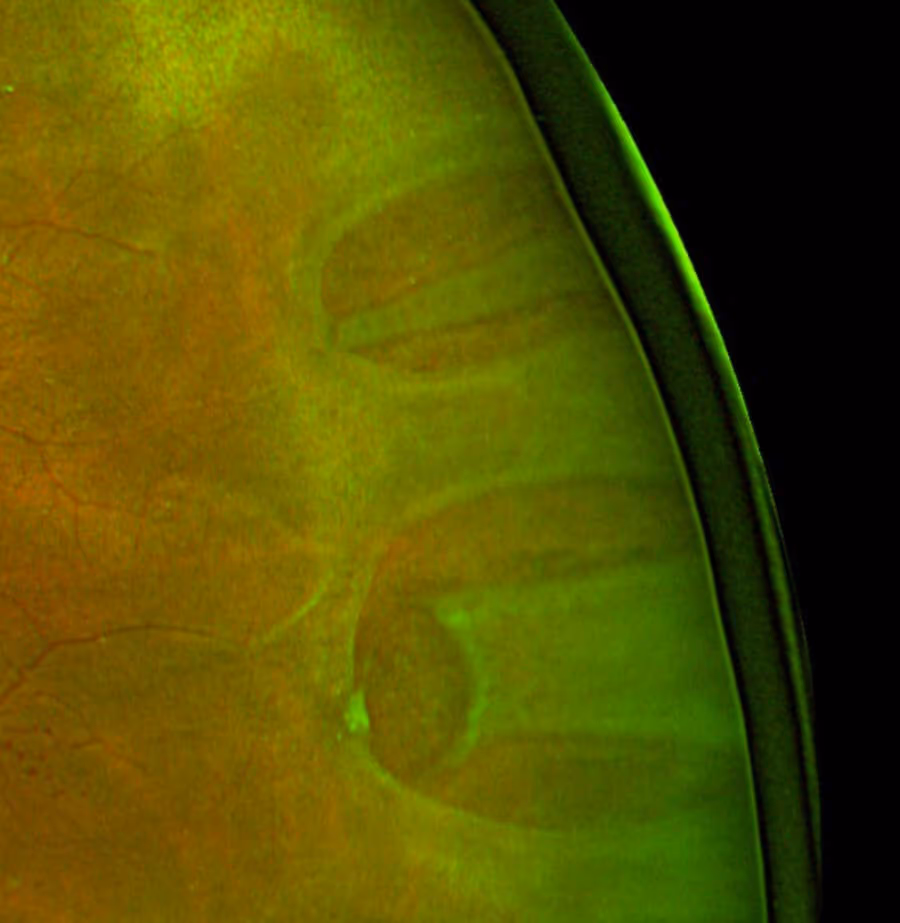

O padrão-ouro para o diagnóstico é o exame de fundo de olho dilatado com oftalmoscópio indireto, realizado por um oftalmologista. É comum associar a depressão escleral, uma técnica que ajuda a visualizar toda a retina periférica e identificar rasgaduras pequenas.

Quando o meio ocular está opaco (catarata avançada, hemorragia vítrea) e impede a visualização direta, podem ser usados: ultrassonografia B-scan (muito útil — mostra a retina descolada como uma membrana flutuante), fotografia de fundo de ampla angulação e OCT para avaliar envolvimento macular.